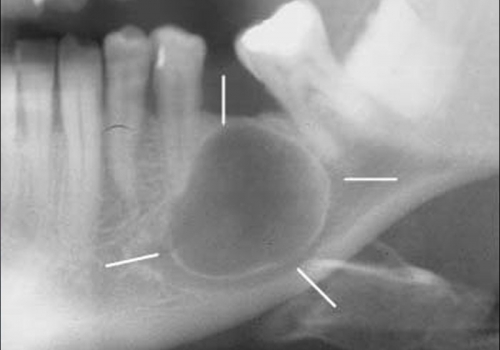

Odontogenik kistlər çənədə ən çox rast gəlinən törəmələrdən olub, başlanğıcını diş orqanından götürür. Bu törəmələr epitel hüceyrə qatı ilə döşənmiş zarla əhatə olunmuş, daxilində isə spesifik maye yerləşən kisəni xatırladırlar. Odontogenik kistlər ya xroniki iltihab nəticəsində ya da inkşaf anomaliyası nəticəsində yarana bilir.

İnkşafı və böyüməsi tədricən baş verdiyindən, bu proses pasiyent tərəfindən demək olar ki hiss edilmir. Yalnız törəmənin ciddi ölçülərə çatması nəticəsində və ya iltihablanması nəticəsində meydana çıxan kliniki əlamətlər nəticəsində aşkarlanır. Əksər hallarda isə çəkilən diş və çənə rentgen şəkillərində təsadüfən rast gəlinir.